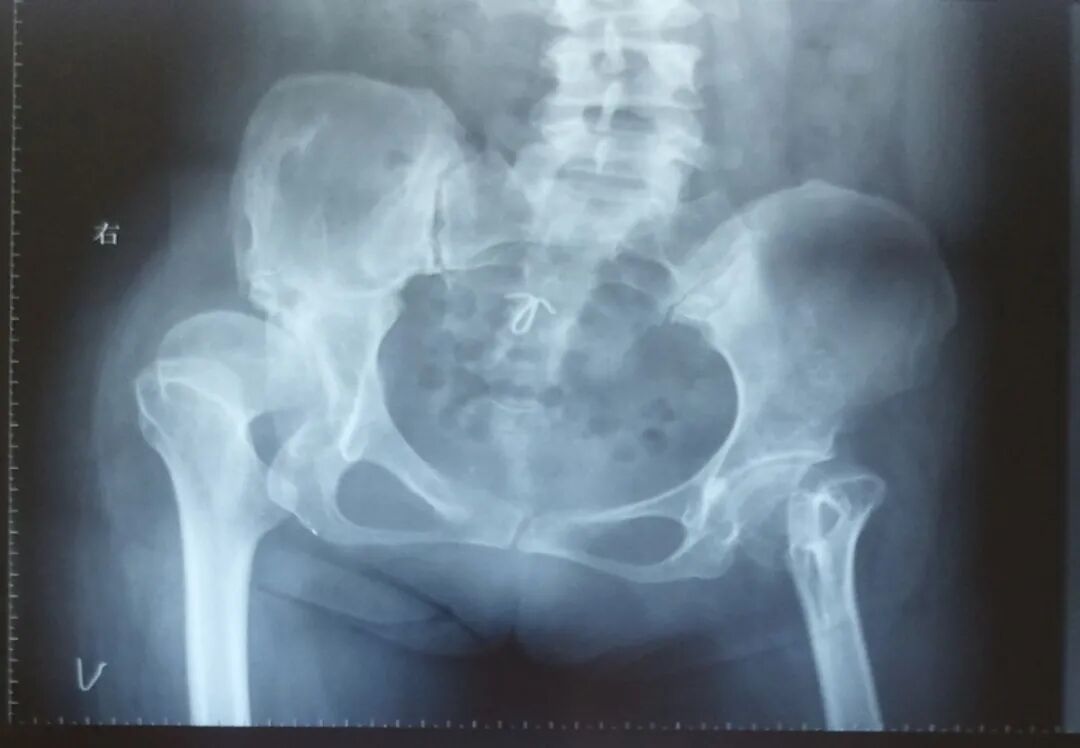

先看病例!

女性患者,48岁,右髋疼痛25年,加重1年

术后5天,脱位

切开复位

术后4月,再一次脱位

屋漏偏遭连夜雨